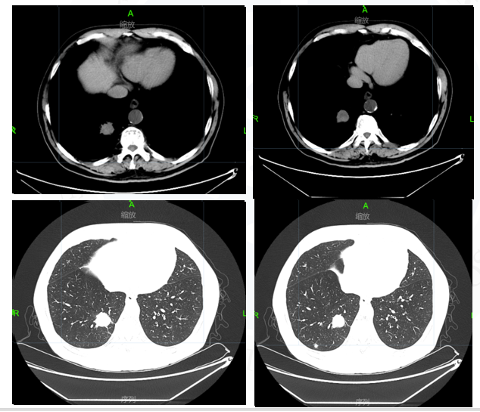

图5胸部CT

√ 2021.06.28胸部CT:右肺下叶后基底段肿块约21×23×21mm大小,右肺下叶后基底段(Img230)见结节影,大小为7×7mm,较前缩小。疗效评价PR。

图7胸部CT